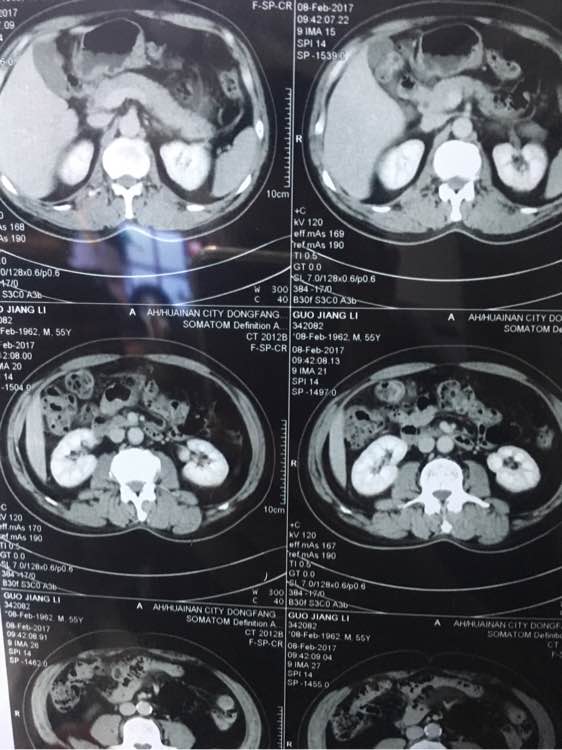

大神看下,几个月前说肠子

几个月前说有点东西,肠子上

兄弟 你拍的有点多啊 全腹部ct?